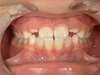

Traitement d’une occlusion inversée par l’éducation fonctionnelle

Après